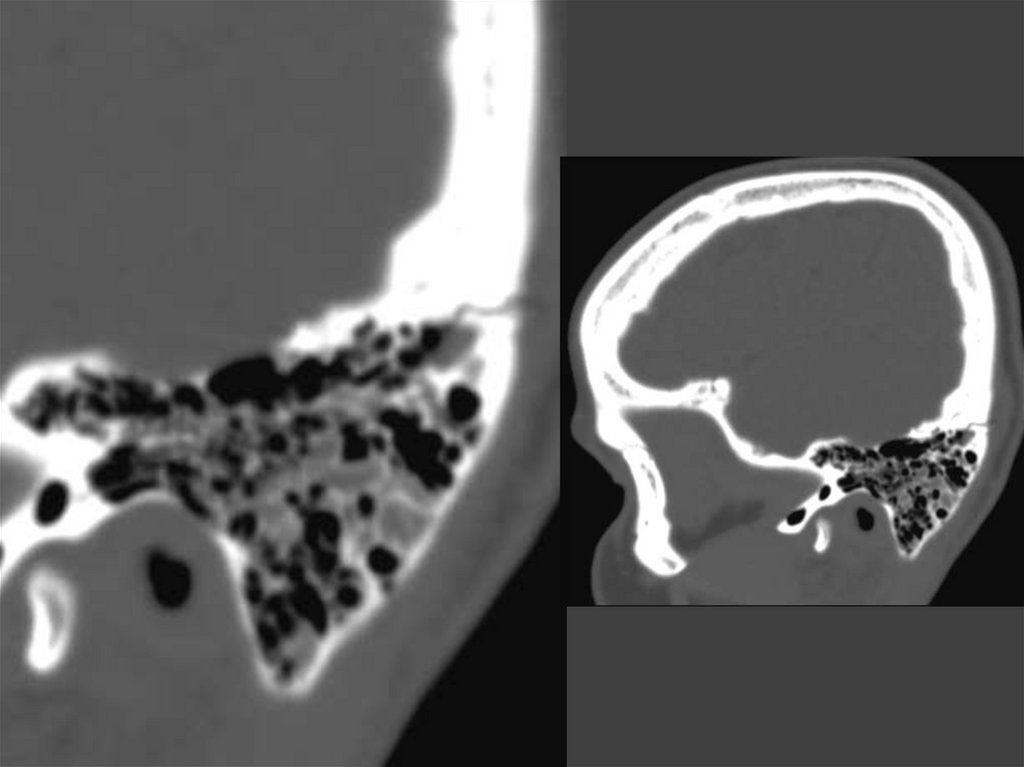

172. Тотальная оссификация лабиринта